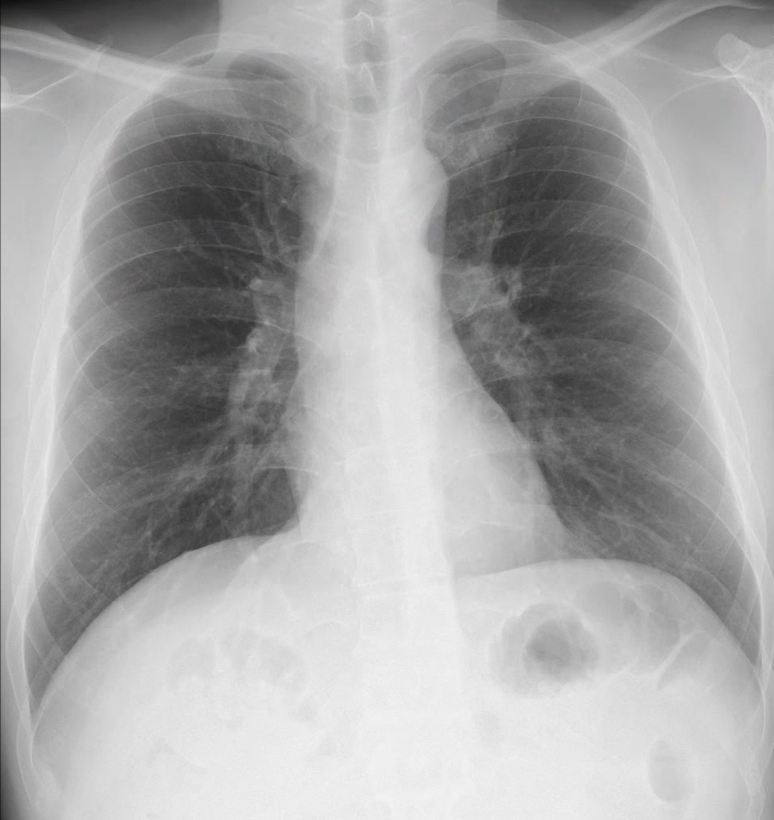

実はこの中に肺がんが写っています。レントゲンですべて見抜くのは熟練医でもかなり難しいものなのです。

「レントゲンで異常がないと言われたけれど、ずっと咳が続いている」という場合、この「死角」や「解像度の限界」に病気が隠れている可能性があるのです。